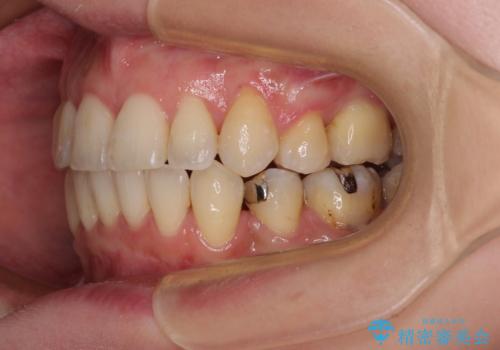

【モニター】上下の八重歯を治したい ワイヤー装置による矯正治療

- クリアブラケット

- 上下前歯のデコボコを気にして来院された患者様です。

デコボコが強いため、非抜歯で矯正をすると出っ歯仕上がりとなるため、上下左右の第一小臼歯4本を抜歯することとしました。